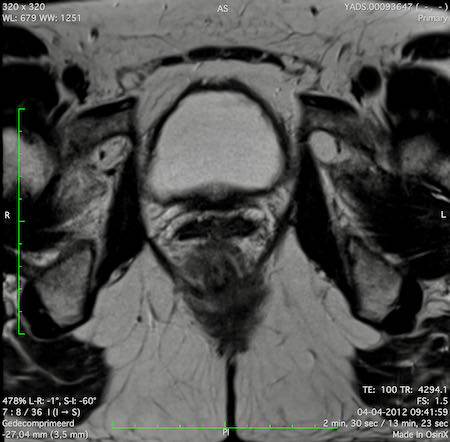

Hình ảnh

Các hình ảnh được cung cấp cho thấy ung thư biểu mô tế bào nhẫn với tình trạng dày lan tỏa thành trực tràng, hình ảnh bia bắn điển hình, và sự xâm lấn mỡ mạc treo trực tràng.